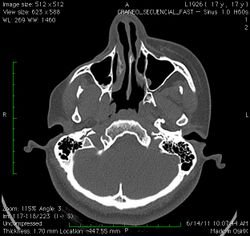

A 3D, soft tissue reconstruction of a CT scan of a 17-year-old girl with Parry Romberg syndrome.

CT scan3D bone reconstruction of a 17-year-old girl with Parry Romberg syndrome.